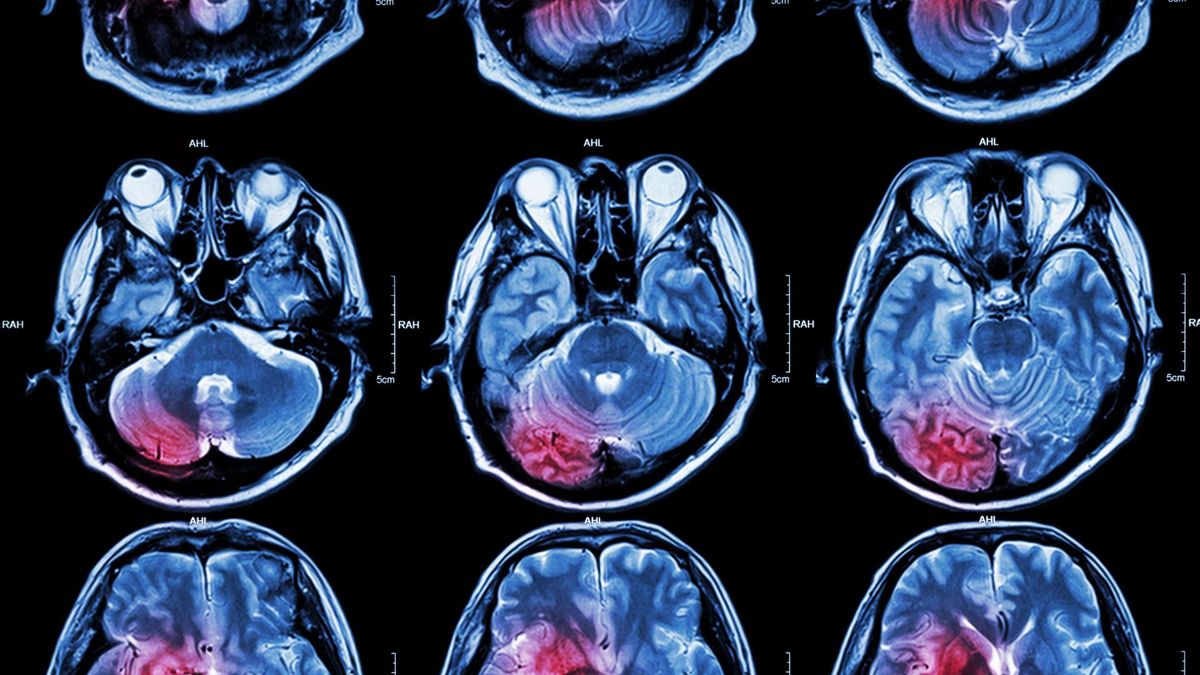

Lekarz zleca wykonanie rezonansu magnetycznego głowy z kontrastem i tomografię komputerową.

Lekarz zleca wykonanie rezonansu magnetycznego głowy z kontrastem i tomografię komputerową. © 123rf.com

Jeśli jest taka konieczność, wykonuje się rezonans magnetyczny głowy z kontrastem i tomografię komputerową. Pozwala to na określenie wielkości guza i sprawdzenie czy występują przerzuty.